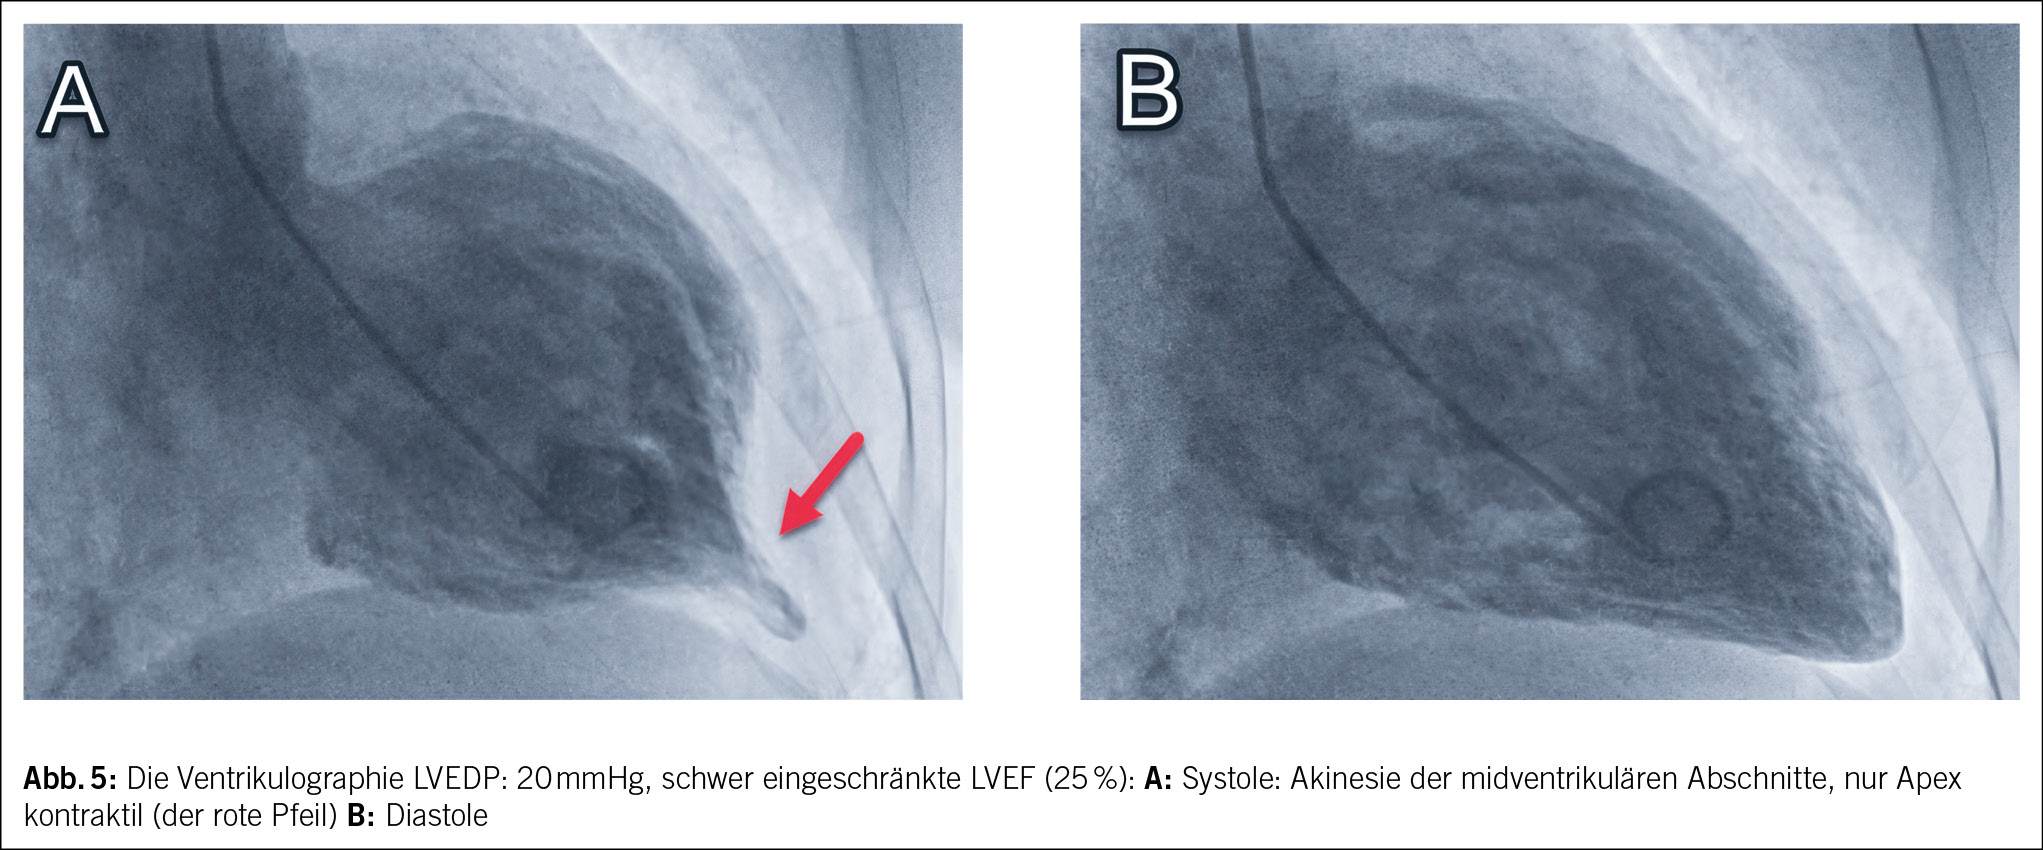

Bei Verdacht auf Myokardinfarkt wurde die Patientin ins regionale Krankenhaus eingewiesen und anschliessend zur Herzkatheteruntersuchung ins Zentrumsspital verlegt. Eine koronare Herzkrankheit konnte ausgeschlossen werden, jedoch zeigte die Ventrikulographie bei einem erhöhten linksventrikulären enddiastolischen Druck vom 20 mmHg (Norm < 15 mmHg) eine schwer eingeschränkte systolische linksventrikuläre Ejektionsfraktion (LVEF) von 25 % (Norm > 55 %) mit Akinesie der midventrikulären Abschnitte (Abb. 5).

Das Krankheitsbild des Takotsubo-Syndroms ist durch typische Beschwerden ähnlich eines akuten Koronarsyndroms mit akuten thorakalen Schmerzen, Dyspnoe sowie erhöhten kardialen Biomarkern gekennzeichnet. Elektrokardiographisch zeigen sich typischerweise ST-Strecken-Abnormalitäten, am häufigsten initial ST-Hebungen und im Verlauf fortschreitende T-Inversionen und QT-Zeit-Verlängerungen (2, 3). Echokardiographisch und in der Ventrikulographie sind typische regionale Wandbewegungsstörungen sichtbar. Die Koronararterien zeigen typischerweise keinen erklärenden Koronarverschluss. Anhand der Regionalitäten lassen sich morphologisch 4 Typen des Takotsubo-Syndroms unterscheiden: den midventrikulären Typ, den basalen und den fokalen Typ sowie den apikalen Typ. Letzterer weist als typisches Bild ein apikales Ballooning infolge der apikalen Akinesie auf und tritt in über 80 % aller Fälle auf (4). Der midventrikuläre Typ ist die zweithäufigste Form, dabei sind die midventrikulären Wandabschnitte akinetisch und die basalen sowie apikalen Segmente hyperkontraktil. Gemäss dem internationalen Takotsubo-Register wird vermutet, dass die LVEF bei atypischem Takotsubo-Syndrom im Vergleich mit dem typischen Takotsubo-Syndrom weniger eingeschränkt ist (5).